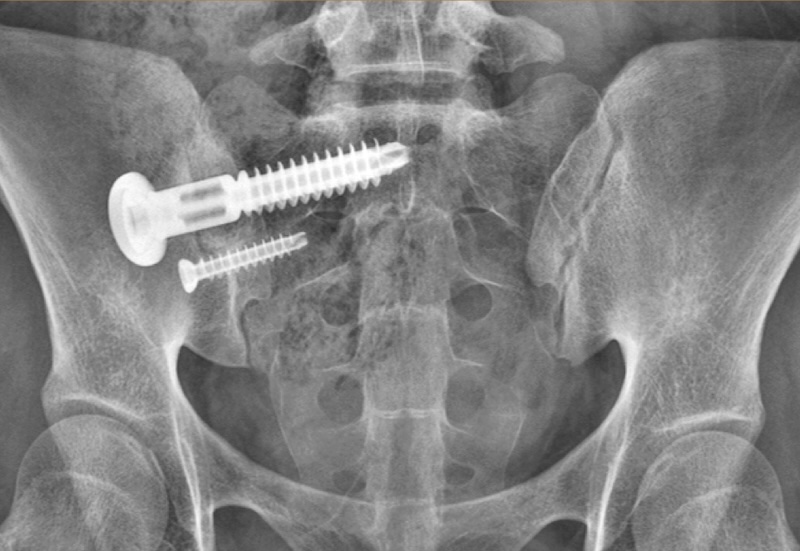

Integrity-SI Fusion System Sacro-Iliac Screw

MANUFACTURER INFO:Integrity-SI Fusion System

The Integrity-SI Sacro-iliac fusion system by OSteoCentric is a minimally invasive lateral SI joint stabilization. It features an etched titanium lag bolt with a large compression washer to provide compression across the SI joint. The Integrity-SI features a large window that spans the SI joint to facilitate bone graft and bony ingrowth. The surface treatment of the screw allows increased bony purchase for osseointegration. The system feautres a proprietary BladeX instrument that facilitates cleaning out and decortication of the SI joint

• Optional secondary anti-rotation screw